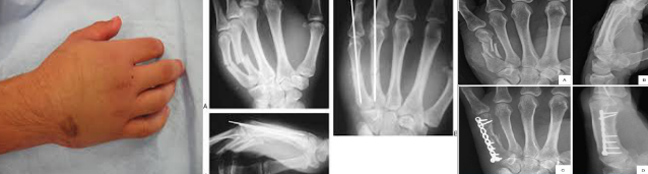

Τα μετακάρπια είναι τα κόκαλα που προηγούνται των δακτύλων και σχηματίζουν το έδαφος της παλάμης. Υφίστανται κατάγματα από άμεση πλήξη, σε πτώση ή από σύνθλιψη.

Mε τον δείκτη ανευρίσκουμε το σημείο ευαισθησίας. Με την πίεση προκαλείται «κριγμός» κι οξύς πόνος. Η διάγνωση επιβεβαιώνεται με ακτινογραφία όταν υπάρχει.

Tα κατάγματα των μετακαρπίων σήμερα χειρουργούνται εύκολα. Όμως εάν ακινητοποιηθεί το κάταγμα με μεταλλικό νάρθηκα (zimmer) ή σε θέση γροθιάς το αποτέλεσμα θα είναι επίσης εξίσου ικανοποιητικό.